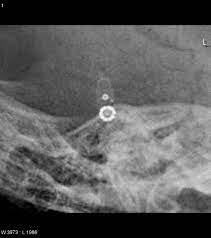

Codman Hakim : Brg Reading Skull Films For Shunt Valve Settings - Codman hakim programmable shunt valve pressure verification wheel.

A Radiographic Appearance Of The Codman Hakim Programmable Valve Set Download Scientific Diagram

According to the ajnr 2010 article by lollis et al, the codman hakim valve is set at 60 mm water (which is the same as the pre mri setting). Codman ® hakim® programmable valve system for hydrocephalus the codman® hakim® programmable valve offers the ability to optimize the opening pressure of a shunt. Codman hakim programmable shunt valve pressure verification wheel. Utah pediatric radiology codman hakim programmable shunt. In vivo, the pressure that the valve responds to is the difference between the. The codman hakim valve is a ventricular shunt valve which can be programmed to open at various csf fluid pressure. The codman hakim programmable valves are supplied without a specific programmed. The codman hakim precision valve is a pressure differential valve constructed to open at a predetermined pressure.